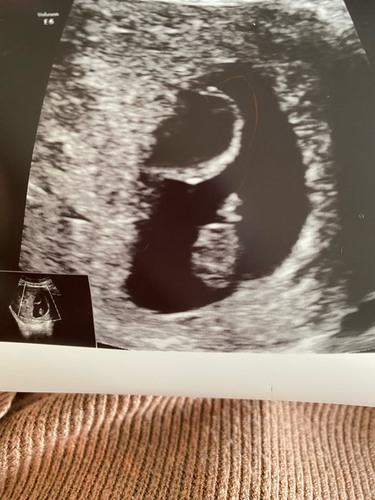

Bijgevoegd de foto! Ik was toen 7+5 weken zwanger.

Hier ook met eerste echo een cyste ontdekt naast de baarmoeder.. dit had ik niet bij mn eerste kindje (nu 5 jaar)

vk heeft samen met collega gekeken en beoordeeld dat er nog geen verdere actie nodig was om gynaecoloog mee te laten kijken, de 23e hebben we de termijn echo, toch wel spannend.. al zeggen ze dat het niks is om ongerust over te zijn. Afwachten dus. (was even vergeten dat zwanger zijn soms zenuwslopend wachten is :) vooral het begin, pfff..)